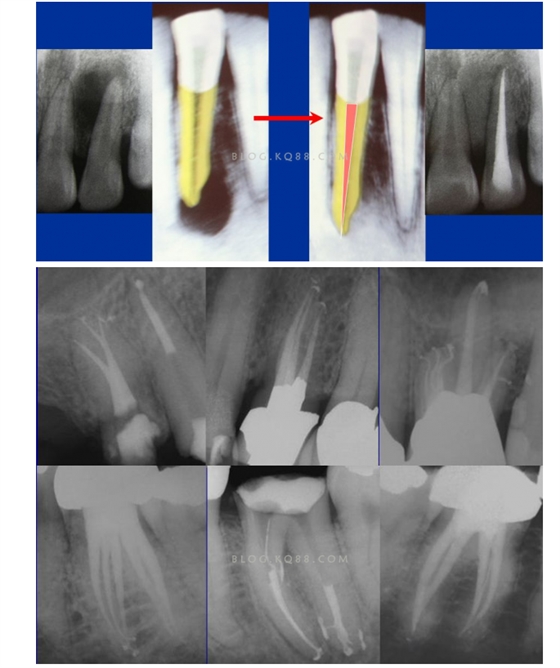

1簡化難度 一個牙齒的根管治療難易程度不單單是根管的彎曲、細小、牙位、是否再治療決定的,開髓的直線進入和根管口的預先恰當處理可以簡化很大的難度,開髓是根管成敗的基礎(chǔ)。對于彎曲根管冠部的直線入口就顯得尤為重要,冠部良好的直線入口可以避免側(cè)穿、臺階、遺漏根管等問題的發(fā)生,冠部直線入口形成的良好情況,取決于醫(yī)生的理念和合理的器械選擇。開髓孔的大小不是由醫(yī)生和患者的意愿決定的,而是由要治療牙齒的髓腔大小決定的。

2相信有更多的根管存在 相信根管的數(shù)目比我們想象的多,根管系統(tǒng)的復雜程度比我們想象的見到的要更復雜,我們只有用盡所有努力和辦法才可能達到預期目標,對于上 牙合 6的MB2來說過去是偶爾有,現(xiàn)在是偶爾沒有,各種文獻報道的比例也不一致,我在培訓班醫(yī)生帶來的離體牙中幾乎沒有見到?jīng)]有的,臨床中也是一樣。對于尋找的方法來說,我覺得相信有才是最重要的,首先相信一定有就會想各種辦法,找到的幾率就會更多。如果有條件在顯微鏡和超聲的配合下效率會更高。

5、預備到多少號結(jié)束根管預備理想的情況應該預備到多大錐度,多少號,預備后根管空間是金字塔還是埃菲爾鐵塔。專家經(jīng)過離體牙根尖切片研究發(fā)現(xiàn)根尖狹窄部遠比想象的要大,如果根管預備太小就會殘留感染物,根管的部分空間就不會預備到,殘留的感染物就會造成治療效果達不到預期目標。只有做到了充分的預備,盡可能的多沖洗才會有好的結(jié)果。

根管治療要做到看清楚,去干凈,充恰滿,封嚴密,就會達到期望的結(jié)果。2200年前的病例只充填了冠1/3可以理解、可以接受;2200年后的今天我們有先進的設(shè)備和材料,就要充填出大錐度高密度的完美結(jié)果。理念決定技術(shù),標準決定技術(shù)的提高和進步。